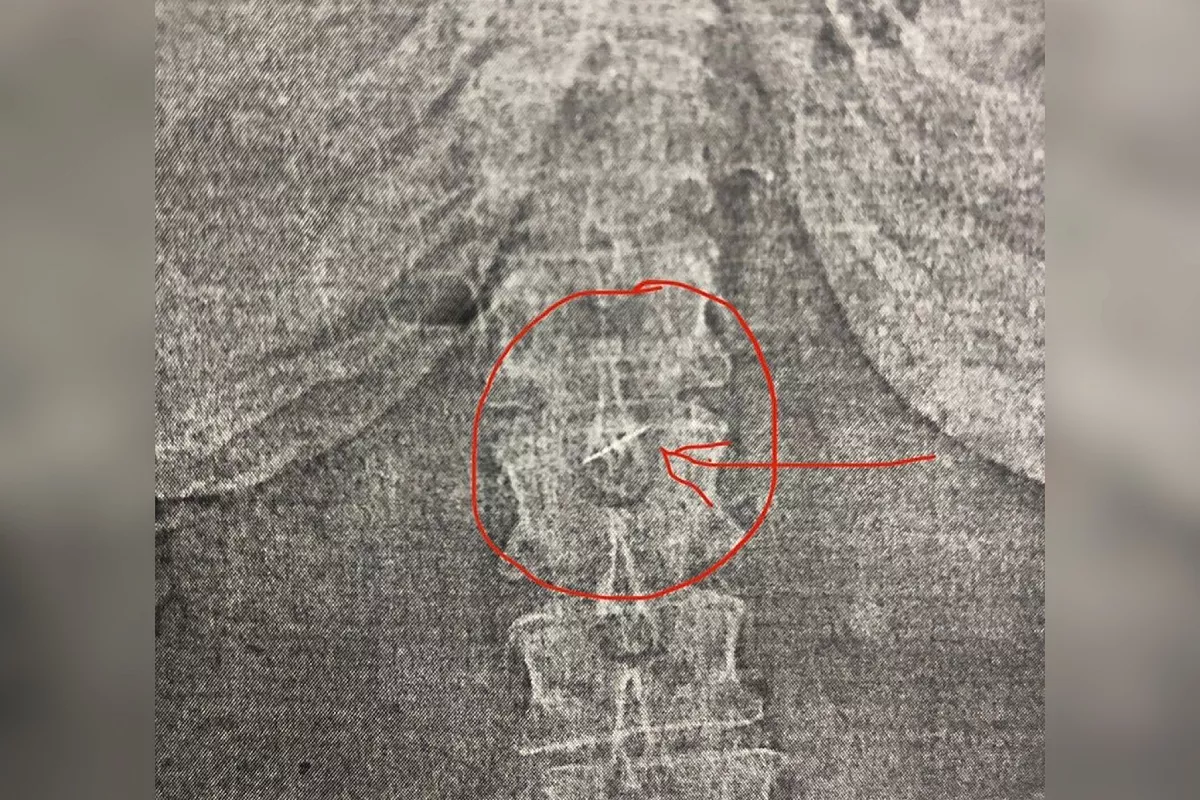

Выяснилось, что пациентка на приеме у стоматолога случайно проглотила инструмент для чистки зубных каналов, длина которого 2,5 см. Во время рентгена его обнаружили в желудке. Инородный предмет, по словам врачей, был крайне острым и опасным, пациентке грозили риск перфорации органа, перитонит и неизбежная открытая операция.

Врачи решили произвести эндоскопическую операцию под местной анестезией.

- Для безопасного извлечения предмета использовали специальную эндоскопическую петлю, при помощи которой стоматологический инструмент извлекли из желудка. Операцию провел заведующий эндоскопическим отделением ГБ № 1 Давид Шагинян. После непродолжительного послеоперационного наблюдения с положительной динамикой пациентку отпустили домой, - отметили в пресс-службе городской больницы №1 Новороссийска.